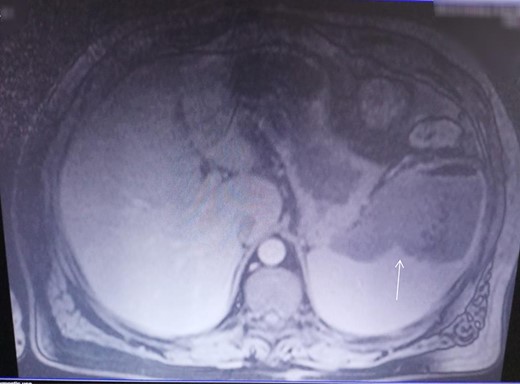

At the admission, erythrocyte sedimentation was 80 mm/h (normal value 3 mm/h), C-reactive protein was 137.7 mg/l (normal value 0.0–6.0 mg/l), leukocytes were 14.2 × 103/μL (normal value 4.0–10.0 × 103/μl), and glycaemia was 14.81 mmol/l (normal value 4.40–6 mmol/l), while other biochemical parameters were normal. The CECT of the abdomen revealed splenomegaly and splenic abscess in the upper pole of the spleen (Fig. 3). No abscesses elsewhere in the body were detected. Systemic hematologic disorders are excluded. Initially, the patient was treated by imipenem- cilastatine. After the admission, on the fourth day, patient underwent open splenectomy. Enterococcus faecalis has been isolated from splenic abscess. On the seventh postoperative day the patient was discharged. The patient was in very good condition a month later after splenectomy. For the lesions on lower legs, based on clinical examination, necrobiosis lipoidica as a diagnosis was confirmed. The disease was in later stage and histopathologic examination was not necessary. This patient was treated by topical administration of steroid cream (Exevate cream 0.05%). After a 2 months follow-up, this treatment was not effective, but continuous to be under surveillance of dermatologists.

CECT investigation revealed abscess and air presence in the upper pole of the spleen.